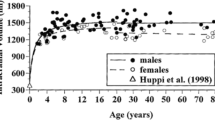

Among the various techniques available for assessing FC, functional magnetic resonance imaging (fMRI) has emerged as the most prevalent method, owing to its unique advantages [9, 10]. Unlike electroencephalography (EEG) and magnetoencephalography (MEG), which directly measure electrical or magnetic brain signals, fMRI detects changes in blood oxygenation—a reliable indirect proxy for neuronal activity. The increased metabolic and oxygen demands during neuronal activation are met by an increase in local cerebral blood flow, a process known as neurovascular coupling. More specifically, the hemodynamic response is characterized by a small initial dip followed by a peak and a post-activation undershoot. During the peak, oxygenated hemoglobin in the activated area has a slightly lower magnetic susceptibility compared to deoxygenated hemoglobin in the vicinity. This subtle difference in magnetic susceptibility alters the local magnetic field, a change detected using multi-volume, dynamic, T2*-weighted pulse sequences. The ensuing signal, known as the BOLD (blood-oxygen-level-dependent) signal, serves as a reliable indicator of neuronal activation [10]. Age-related changes in the BOLD signal have been reported and are related to brain maturation. Compared to adults, the BOLD hemodynamic response to brain activation in infants is characterized by smaller amplitude and delayed time to peak, with preterm infants exhibiting an even more delayed response than full-term infants [11,12,13,14]. Furthermore, the BOLD signal characteristics change throughout childhood and adolescence as the brain continues to develop [15]. These age-dependent variations necessitate careful consideration when analyzing and interpreting FC across different pediatric age groups.

Research indicates that the FC of a child’s brain becomes more similar to that of an adult as they age, with significant changes occurring during adolescence [5, 119]. This shift is characterized by a trend towards increased correlation strength between distant brain regions, reflecting a transition from a local to a more distributed architecture [5]. This findings suggests that there is a trend towards increased correlation strength between distant brain regions during this developmental phase [6]. This shift in FC reflects the maturation process, where higher-order cognitive functions are fine-tuned and specialized. The primitive architecture observed in certain brain networks in younger children gradually evolves into a more integrated and mature configuration during adolescence, contributing to the overall development of cognitive abilities [6].